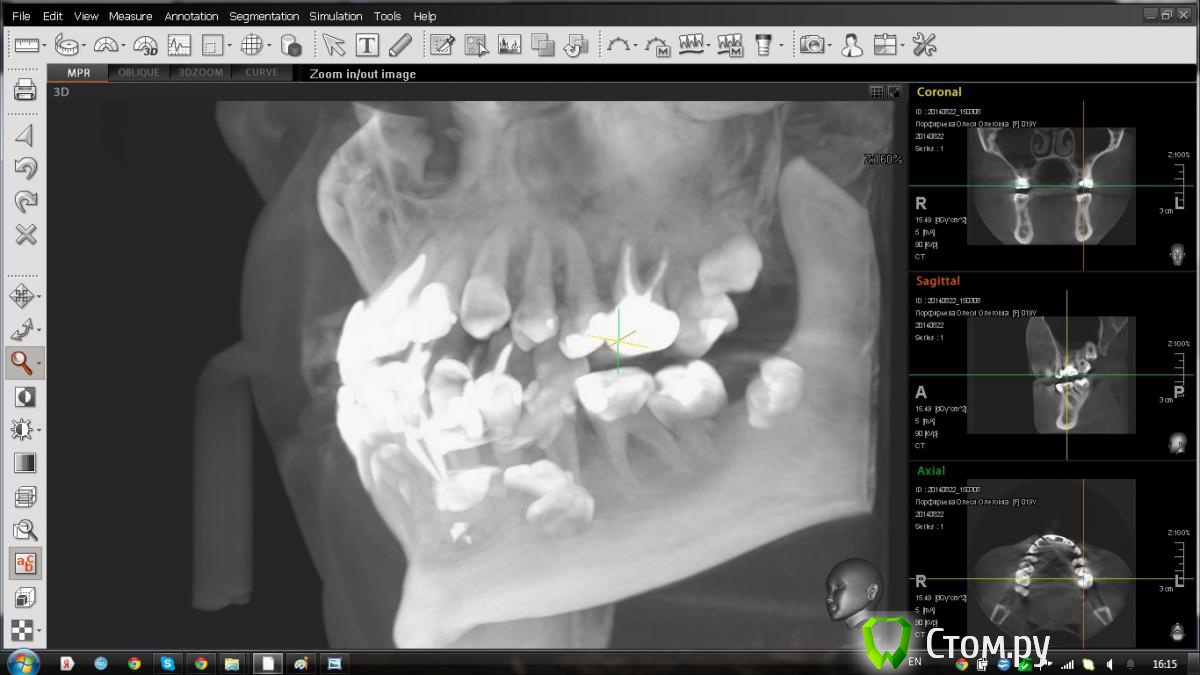

jm3300 Опубликовано 9 сентября, 2014 Автор Поделиться Опубликовано 9 сентября, 2014 вот, набросал Ссылка на комментарий

АнтонТЛТ Опубликовано 9 сентября, 2014 Поделиться Опубликовано 9 сентября, 2014 я понял что это)))это артефакт от зуба, обратите внимание на правую сторону, там в пазухе тоже зуб есть, после эндодонтии)) Ссылка на комментарий

jm3300 Опубликовано 9 сентября, 2014 Автор Поделиться Опубликовано 9 сентября, 2014 я понял что это)))это артефакт от зуба, обратите внимание на правую сторону, там в пазухе тоже зуб есть, после эндодонтии))я об этом думал,но как то не похоже. а жевачка рентгенконтрастна? Ссылка на комментарий

Kostoprav Опубликовано 9 сентября, 2014 Поделиться Опубликовано 9 сентября, 2014 верьте все же кт, а 6-ку пока не поздно на вынос! Ссылка на комментарий